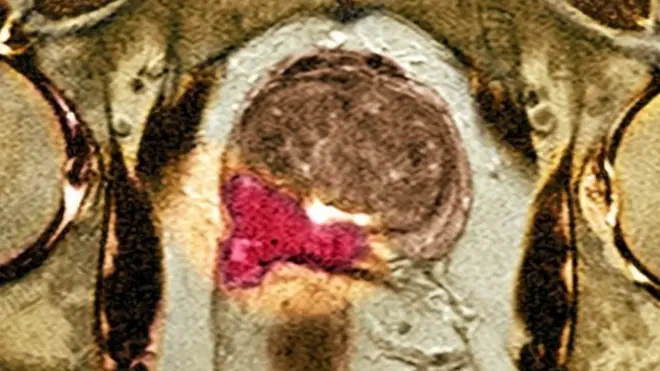

Şəklin mənbəyi, Getty Images